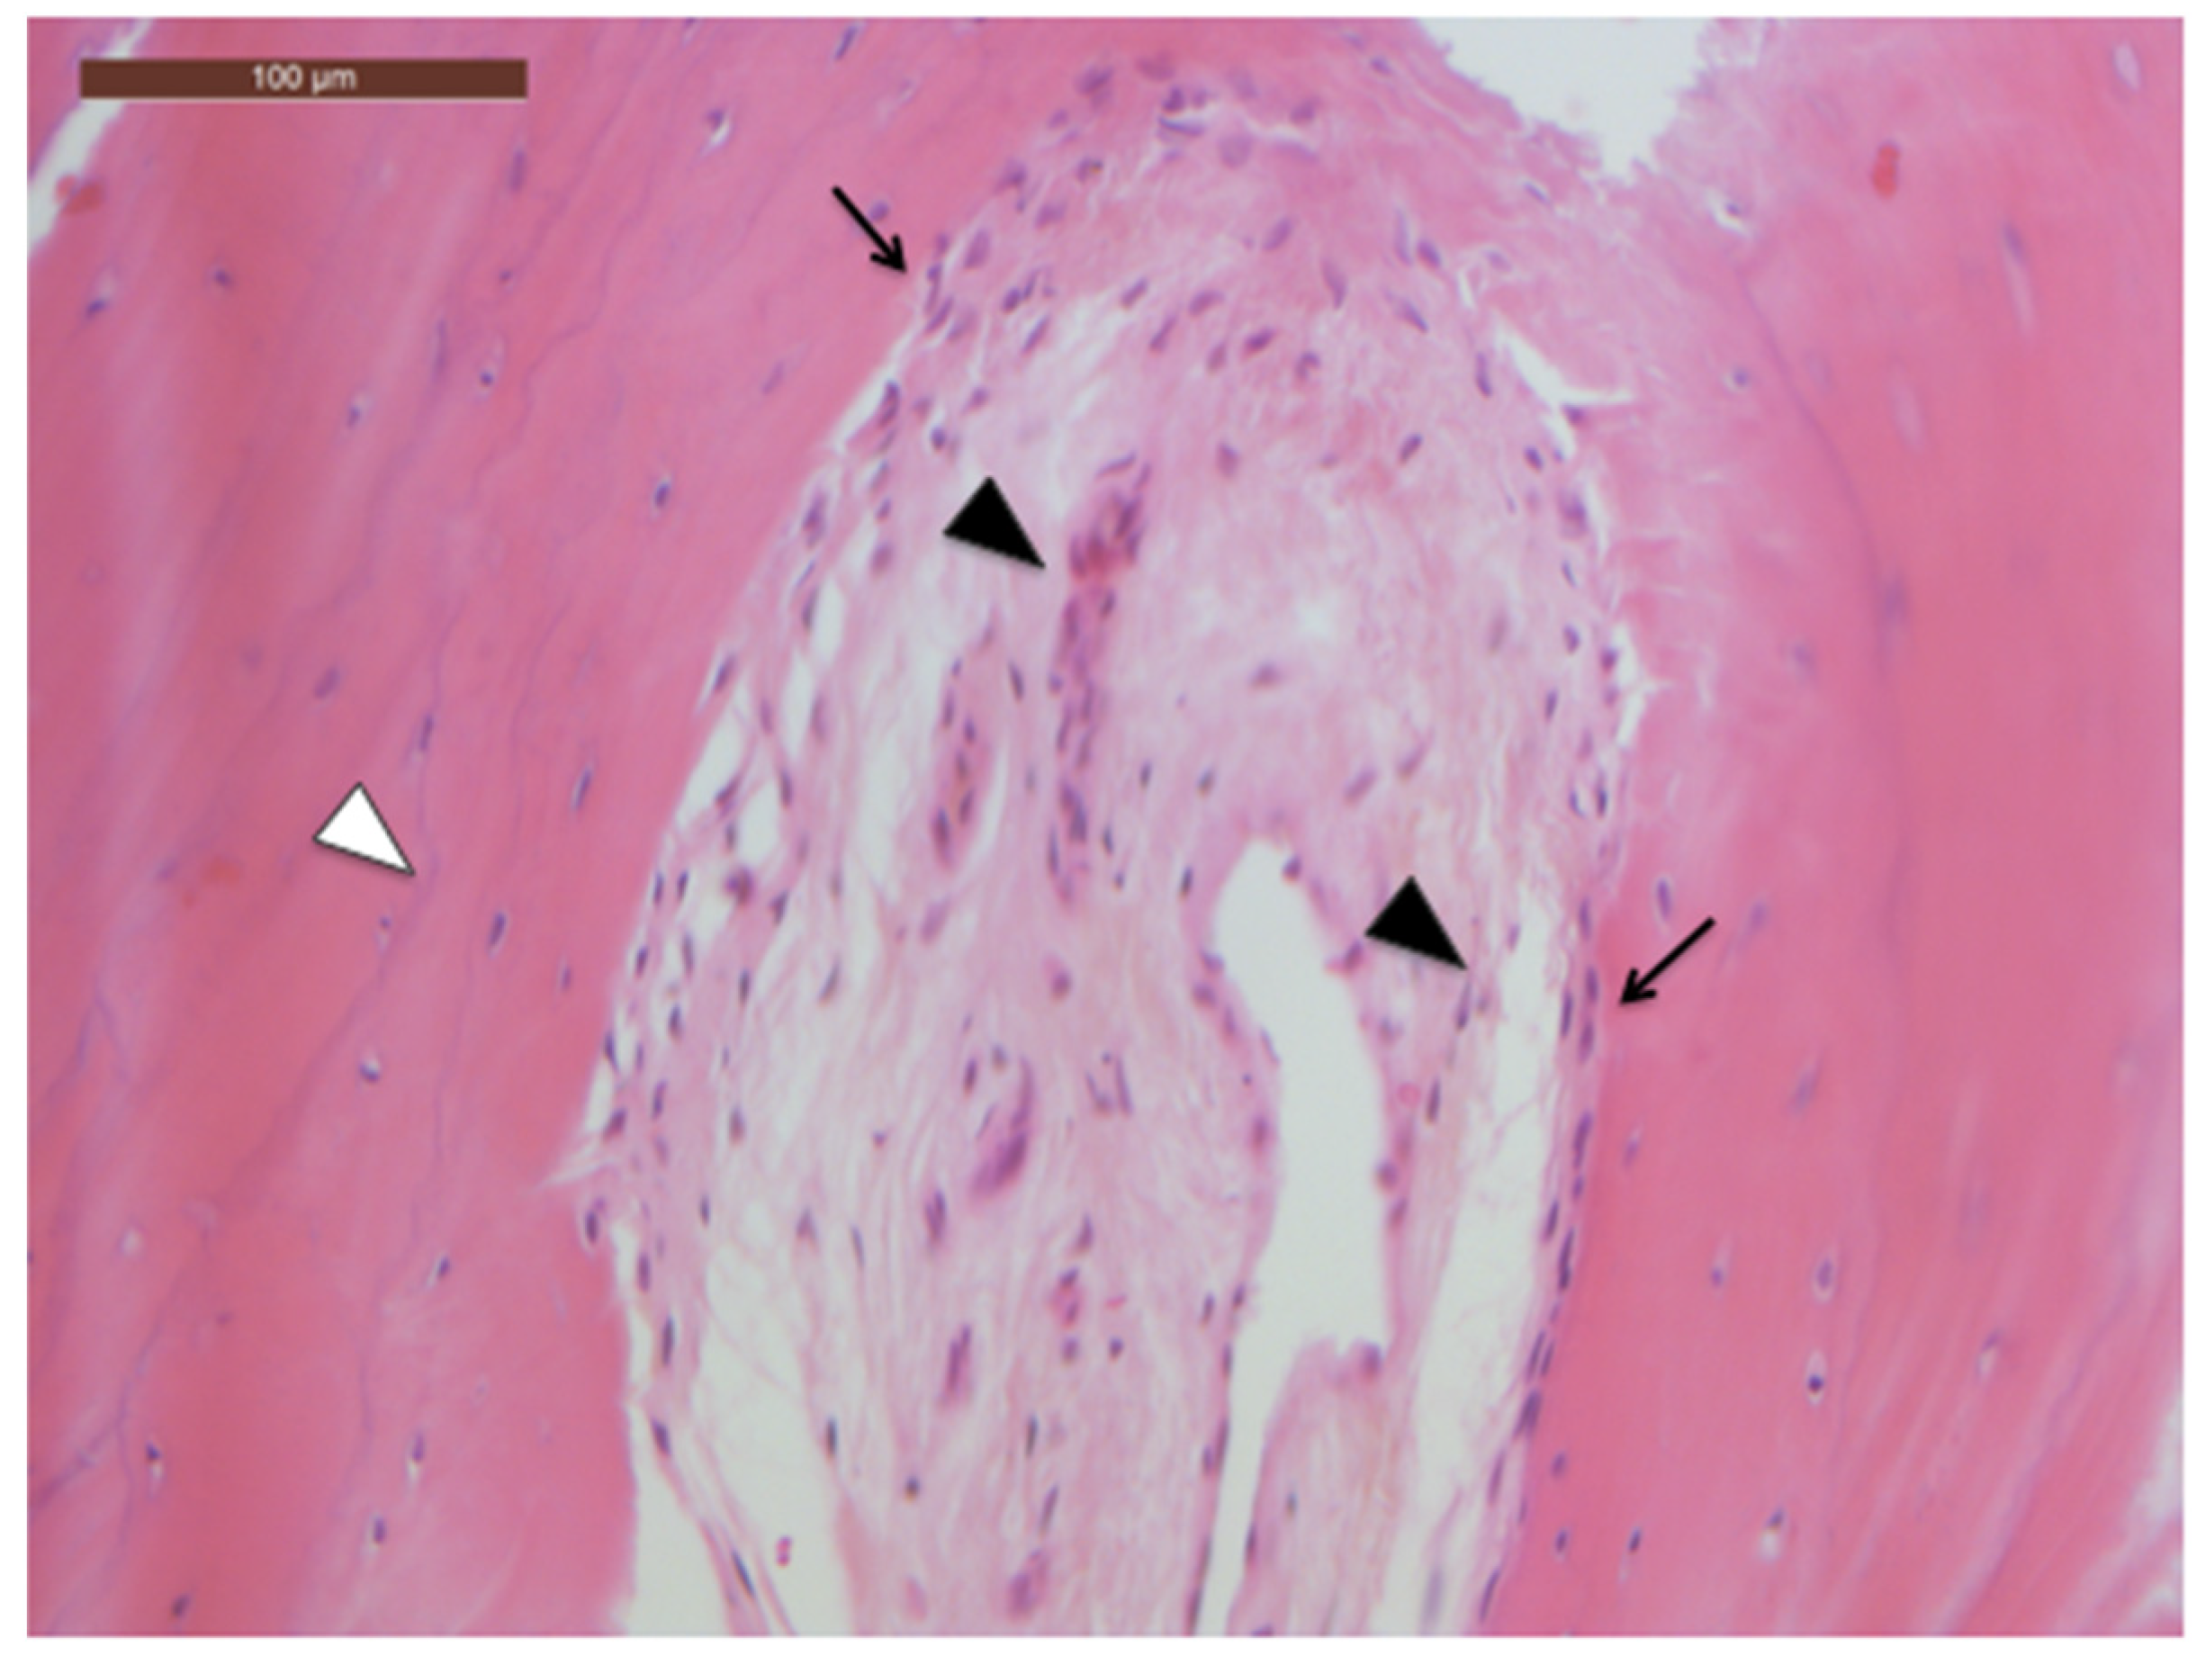

No frank histological findings of bone necrosis were observed in the bone specimens collected during surgery. Interestingly, alveolar bone samples showed aspects of physiologic cellularity and microarchitecture (Figure 4).

Figure 4. Histologic features of the alveolar bone specimen: normal alveolar bone pattern with lamellar bone regular microarchitecture (white arrowhead) and cellularity; the inter-trabecular space is filled with fibrous and adipose tissue infiltrating the medullar space (black arrowheads); viable osteocytes are detected at the trabecular bone surfaces (black arrows). (Hematoxylin–Eosin stain, scale bar magnification: 100 μm).